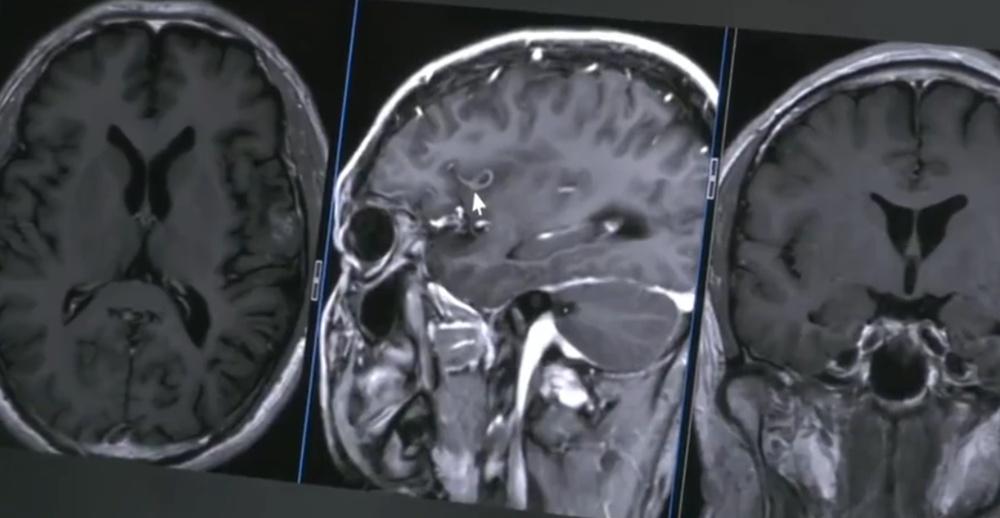

綜合《半城晚報》等內地媒體報道,37歲男子於6月7日和朋友相約到東莞釣魚,下午1點突然感覺嘴巴不受控制地張開,不僅無法說話,就連腦袋也不受控制地向左抽搐點頭。男子說,當時頭腦清醒,但無法用言語表達,所以只能以手心寫字請朋友幫忙叫救護車,但上車前症狀已有所改善。經多家醫院檢查,發現可能是寄生蟲所致,直到他到了廣東三九腦科醫院,神經外二科副主任醫師張旭標才判定他是裂頭絛蟲的幼蟲感染,位置就在大腦掌管語言產生與表達控制的區域。透過影像可以看到蟲體正緩慢向大腦深部移動,因此必須立刻做手術。